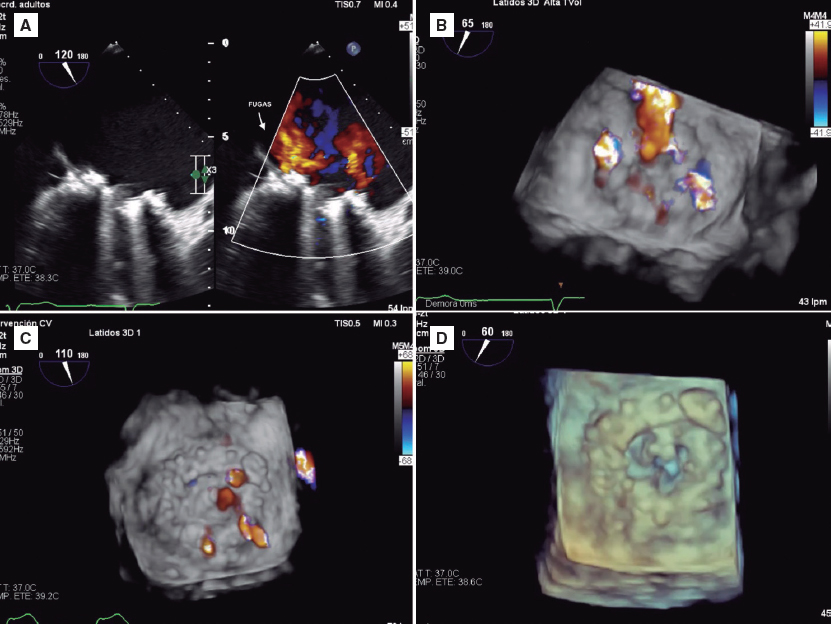

En 2019 se presentó nuevamente con capacidad funcional NYHA III-IV y anemia hemolítica. El ecocardiograma tridimensional mostró 2 fugas paravalvulares mitrales graves (figura 2A,B) (vídeo 1 del material adicional).

Figura 2.

Se realizó un abordaje percutáneo. Vía punción transeptal se construyó un circuito venoarterial anterógrado con guía hidrófila de 0,035 pulgadas (figura 1A,B) (vídeos 2 y 3 del material adicional) y se implantaron 2 dispositivos Amplatzer Vascular Plug III de 12/5 mm (figura 1C) (vídeos 4 y 5 del material adicional), finalizando con 9 dispositivos del mismo tipo rodeando la circunferencia protésica (figura 1D y figura 2D) (vídeo 6 del material adicional). El procedimiento se finalizó sin complicaciones. La ecocardiografía transesofágica durante la intervención mostró una reducción de las fugas paravalvulares mitrales, cuantificadas como insuficiencia leve (figura 2C) (vídeo 7 del material adicional). El paciente evolucionó favorablemente, lo que posibilitó el alta hospitalaria en clase funcional NYHA II-III, con corrección de la anemia (hemoglobina de 12 g/dl) y seguimiento ambulatorio.